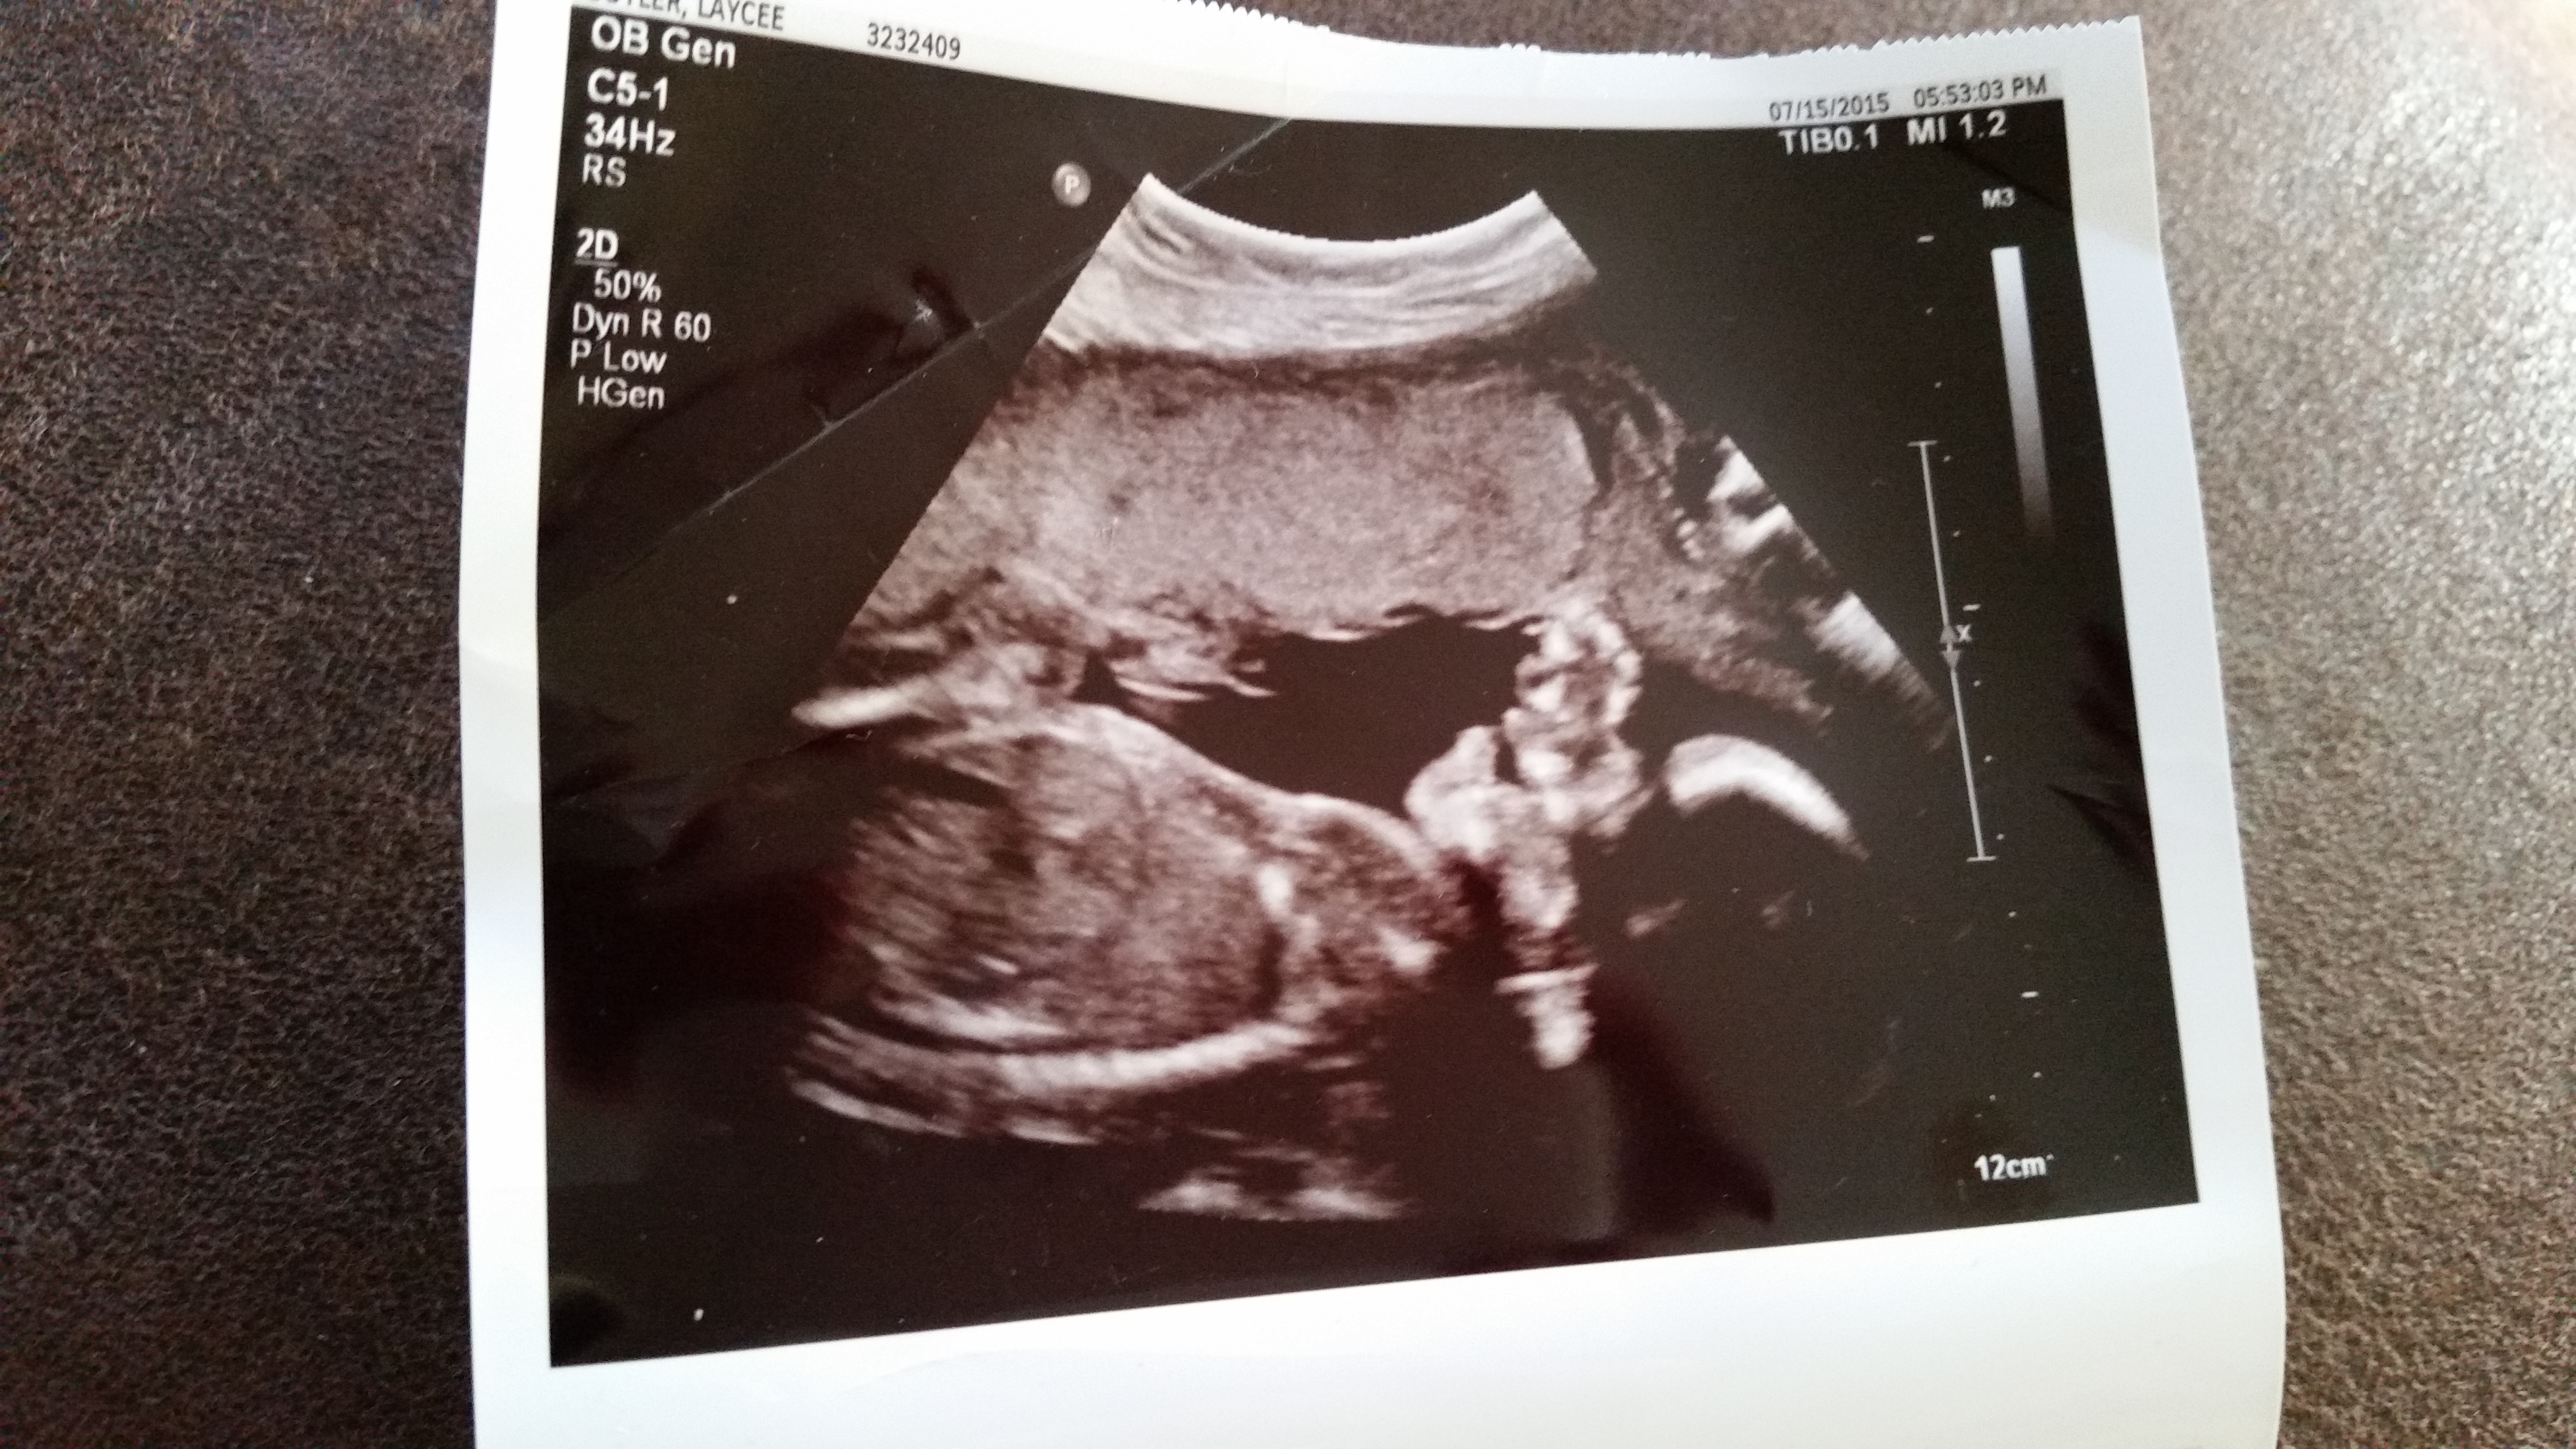

21 week ultrasound hoping tech was wrong...